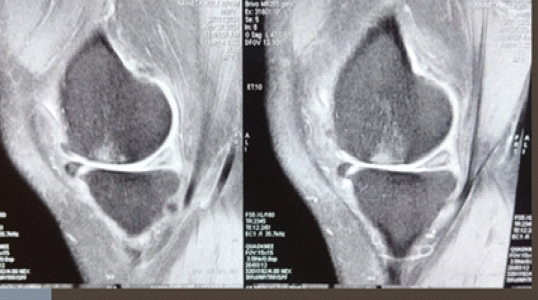

Figure 4: Post-operative magnetic resonance imaging 1 year after minced cartilage implantation.

We initiated the arthroscopic autologous MCI technique with a diagnostic arthroscopy to assess the cartilage defect. Healthy cartilage was then arthroscopically harvested from the defect using a soft tissue shaver connected to an autologous tissue collector (GraftNet: Arthrex), ensuring minimal enlargement of the defect after preparation. The calcified layer was removed, but subchondral drilling was not performed. The harvested cartilage was minced into small fragments, resulting in a paste-like consistency. Minced cartilage was then mixed with platelet-rich plasma (PRP) in a 1:3 ratio. The resulting mixture was loaded into an applicator. Autologous thrombin was generated from additional PRP using a specific device (Thrombinator: Arthrex). After thoroughly drying the joint, the defect was filled with the cartilage-PRP mixture using the applicator. Following a short waiting period, the knee joint was moved through a range of motion to confirm graft fixation over the chondral defect (Fig. 1, 2, 3, 4).